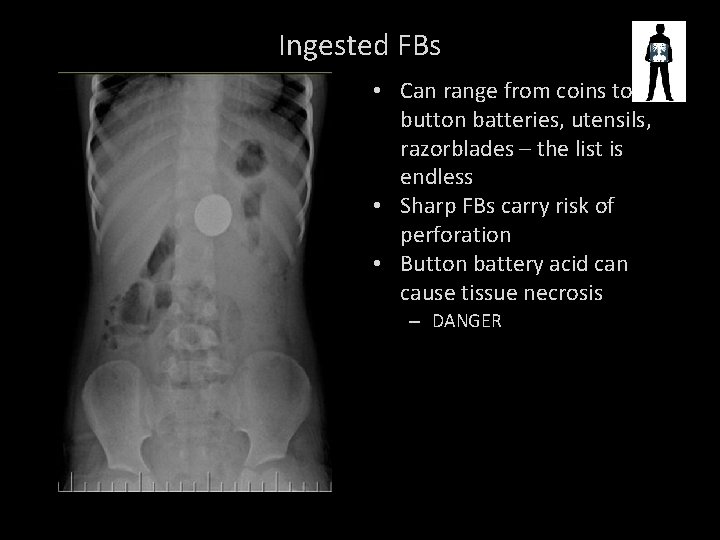

COIN

Ingested FBs • Can range from coins to button batteries, utensils, razorblades – the list is endless • Sharp FBs carry risk of perforation • Button battery acid can cause tissue necrosis – DANGER